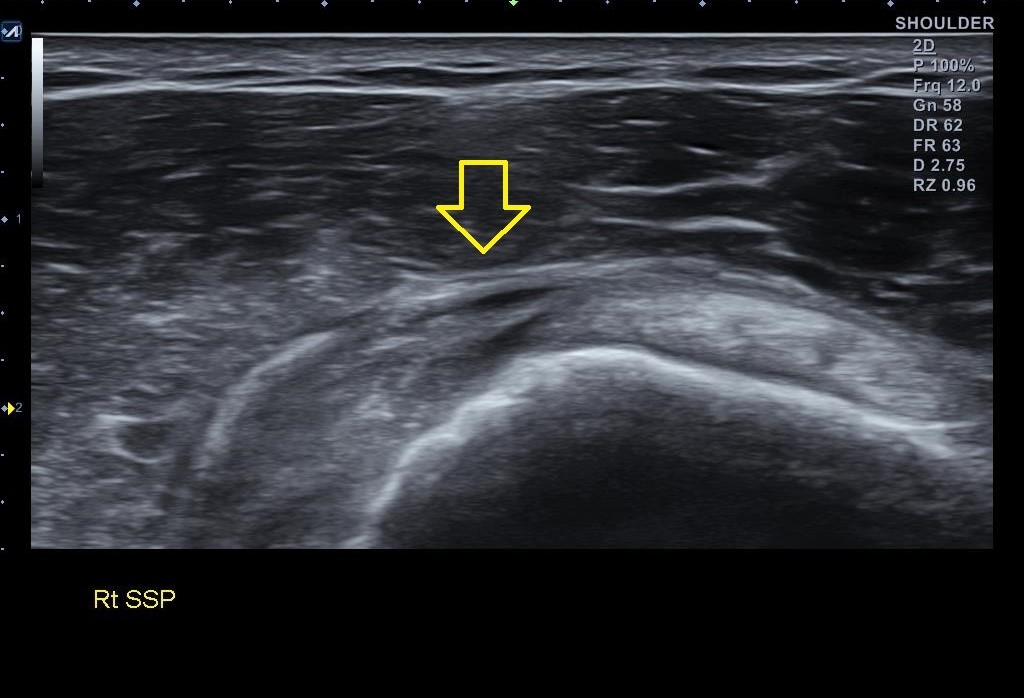

골극이 보이는 상완골 대결절 부위는 극상근 힘줄의 부착부위입니다. x-ray상에 이상 소견이 보인다는건 극상근 힘줄에도 문제가 있을 가능성이 높다는 이야기죠. 힘줄 상태를 확인하기 위해 초음파 검사를 진행했습니다. 결과는...

나 : 초음파 검사 결과를 보니까.... 회전근개 중 극상근이라는 힘줄 파열이네요.

나 : 초음파 검사상 파열 범위와 길이가 아주 심하진 않아서 우선 보존적 치료를 좀 해보고 4주 간격으로 초음파 검사를 몇번 해보면서 지켜봐야 할거 같네요. 지금보다 심해지면 MRI 촬영이 필요할 수 있습니다.